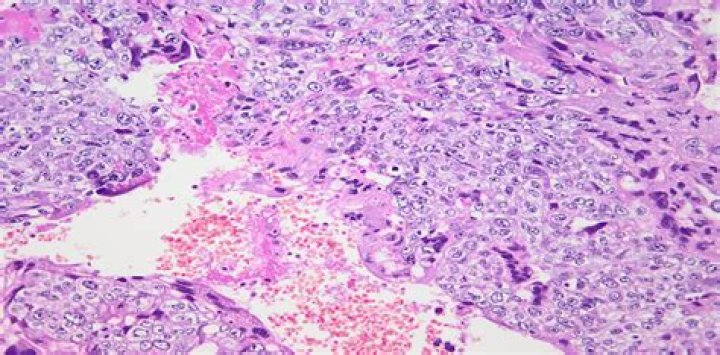

Overview. Choriocarcinoma of the testis is a germ cell tumor that is rarely identified in its pure form; it is more often seen as a component of a nonseminomatous germ cell tumor.

Pure testicular choriocarcinoma is an extremely rare subtype of nonseminomatous germ cell tumor, accounting for less than 1% of all germ cell tumors and only 0.19% of all testicular tumors. It is a highly aggressive malignant tumor with early multiorgan metastasis and poor prognosis.

Invasive mole is unlike choriocarcinoma, the latter is without the presence of chorionic villi. It is important to distinguish between invasive mole and choriocarcinoma, as the former has a more favorable outcome.